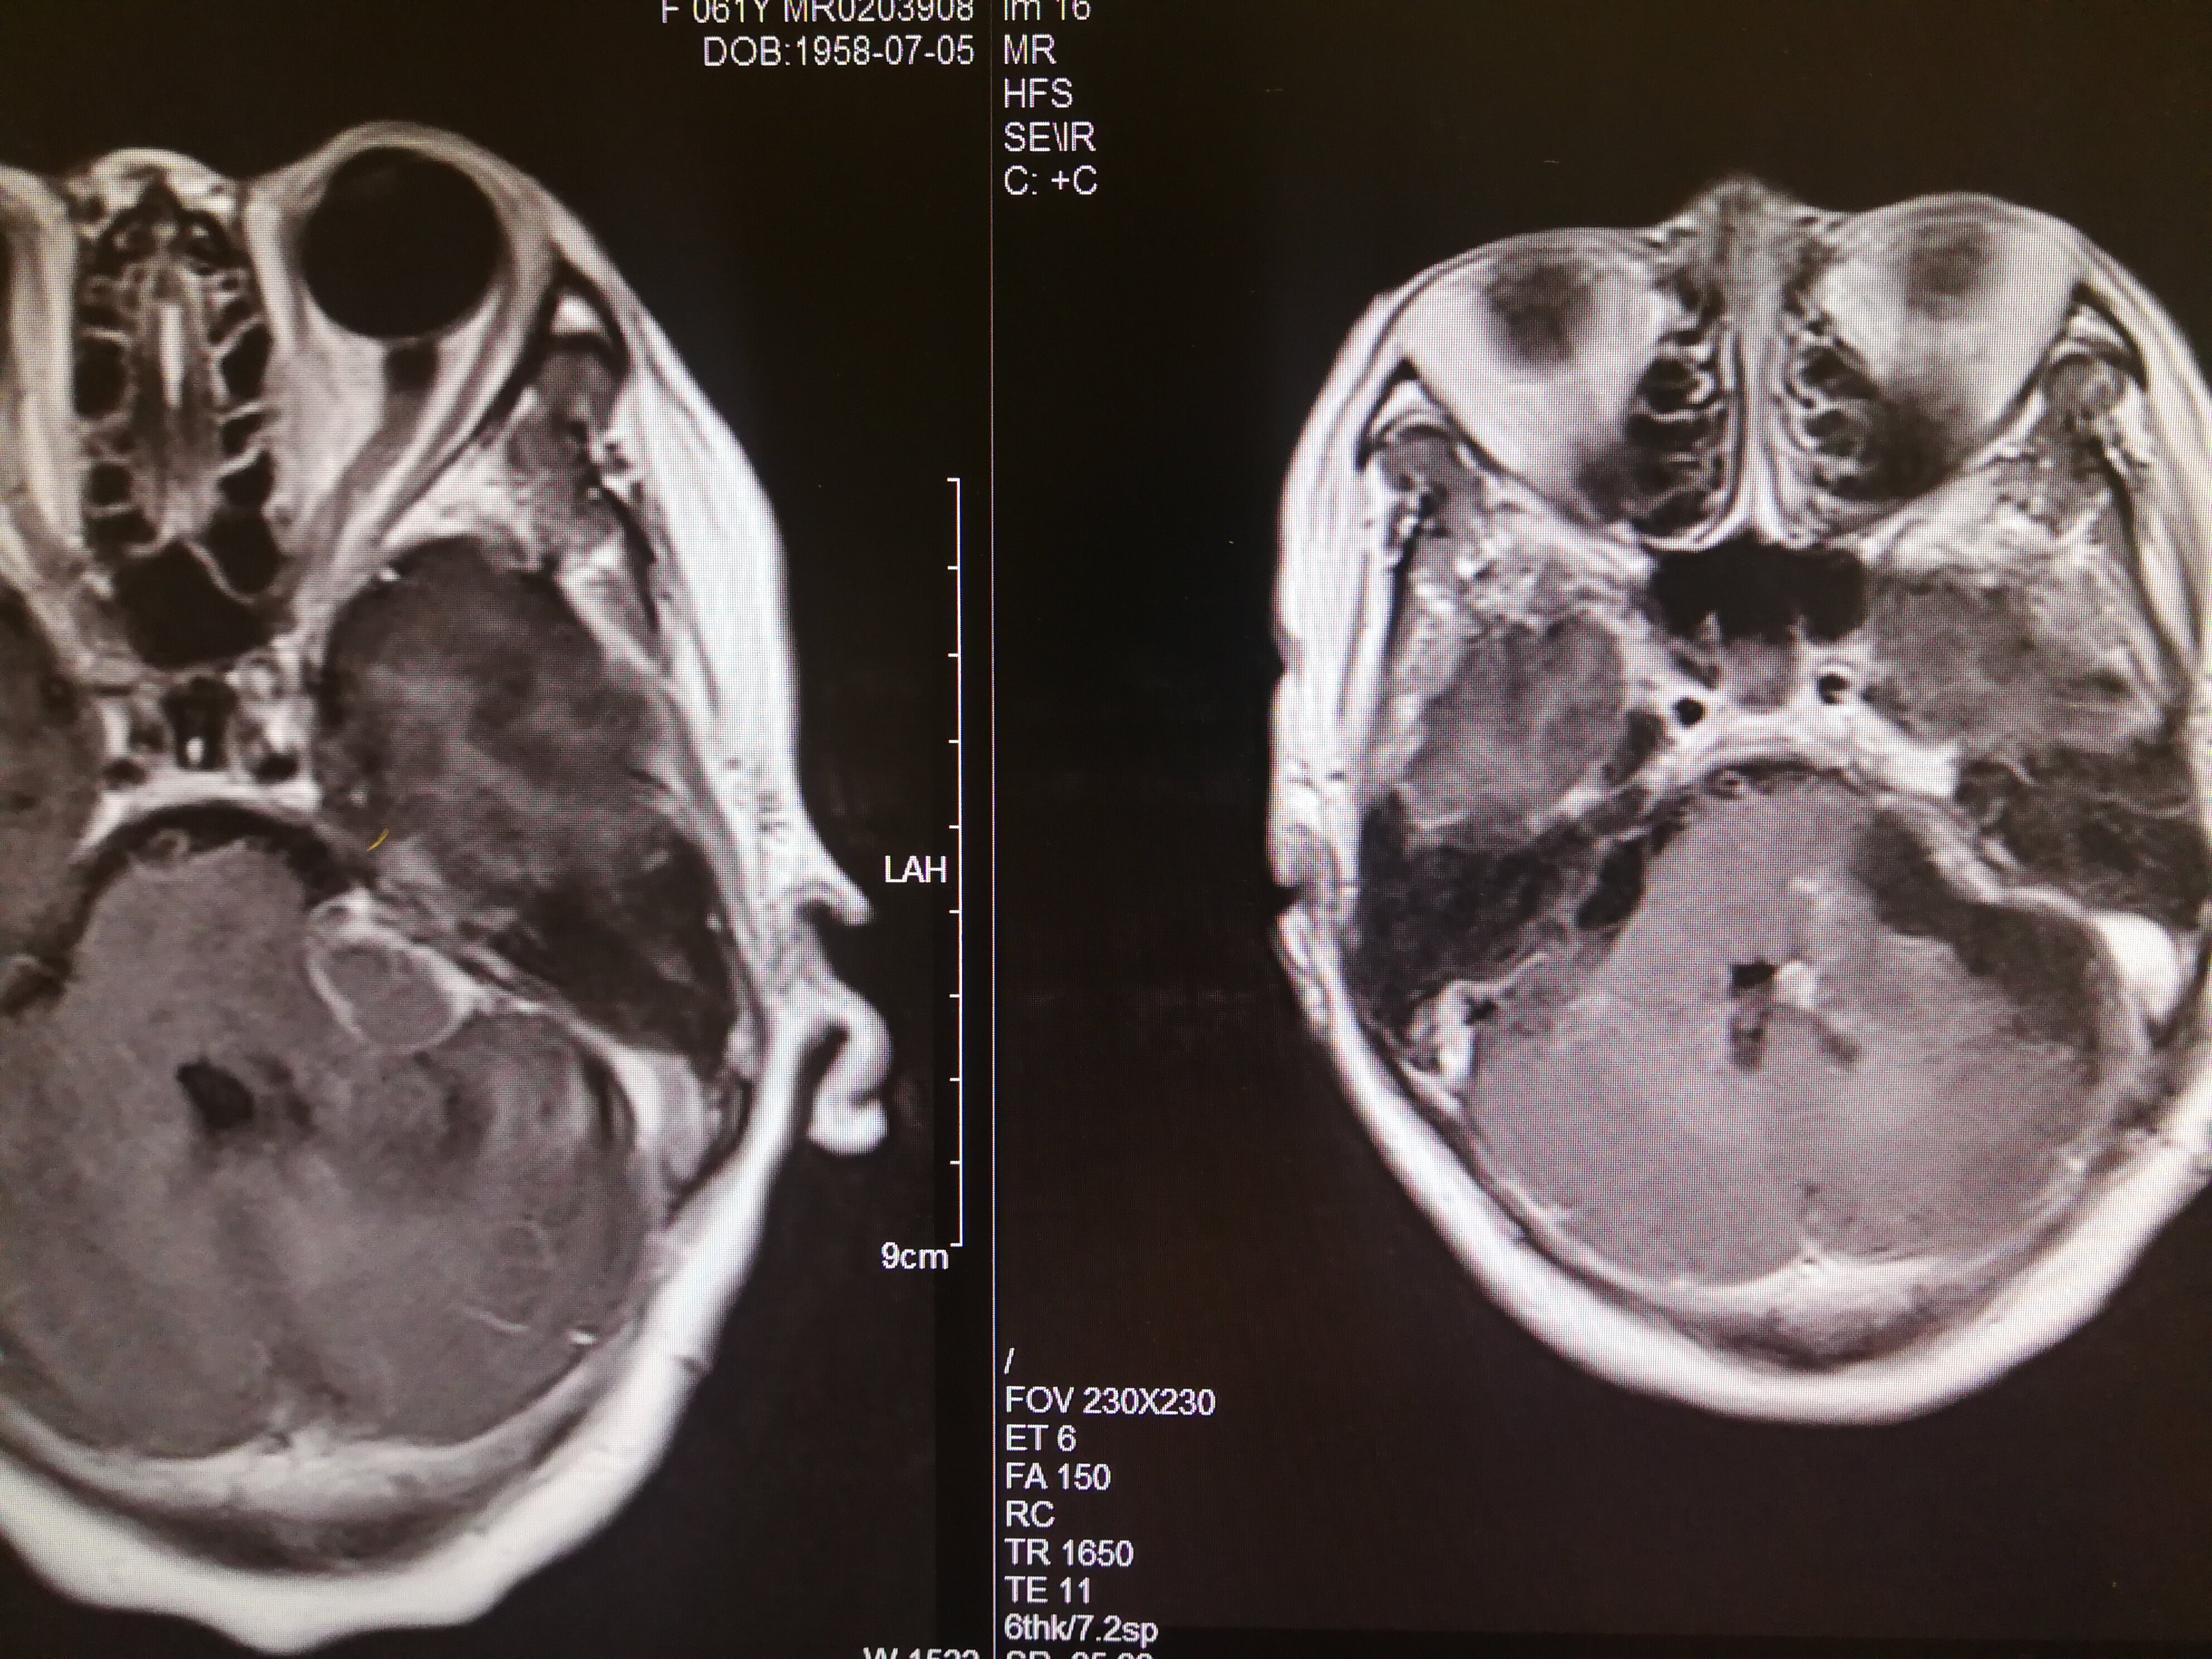

手术治疗听神经瘤是最主要的治疗方式,目前听神经瘤的手术已经非常成熟,只要没有明显的手术禁忌症首先应考虑手术治疗,并要求在电生理监测条件下完成手术,这样可以最大限度地保护面神经功能。以下是几例我们做的听神经鞘瘤手术前后核磁共振片子对照,除手术后听力不能恢复外,没有面瘫,脸部麻木,吞咽困难等颅神经症状,也无其他较明显的手术并发症发生。